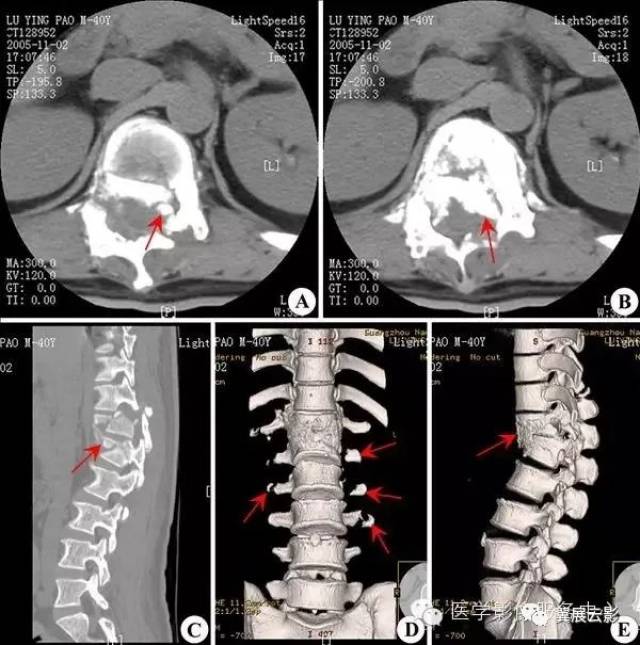

【珍藏】150种骨关节系统影像诊断

独立值班了 这些骨折你都看出来了吗(附注解)